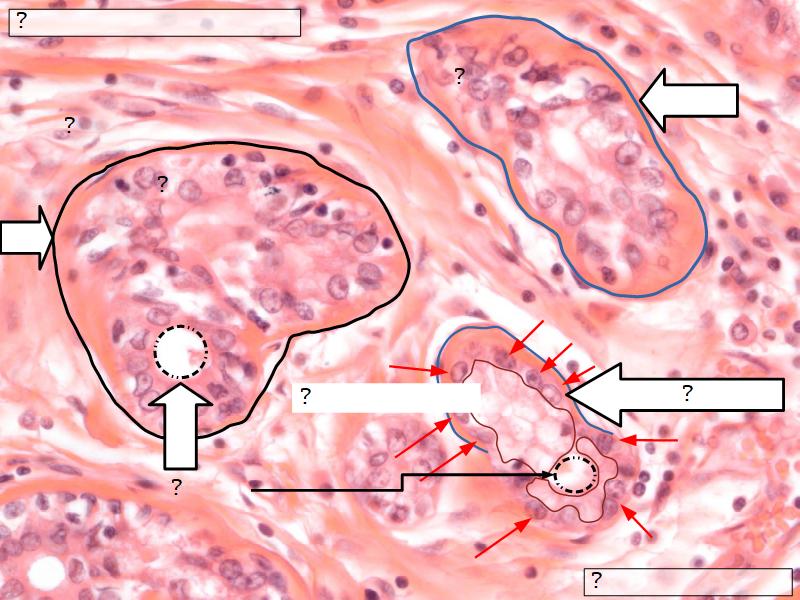

Q06: Epithelium

- Is bordered by a ______.

- Rests on a ______.

Q06: Epithelium

- Is bordered by a lumen.

- Rests on a basement membrane.

Structures

List the structures and cells found in the mammary gland.

Structures

- Lactiferous sinuses

- Stratified squamous near opening on skin

- Stratified cuboidal other parts

- Lactiferous ducts

- Stratified cuboidal

- Myoepithelial cells

- Underlie lactiferous ducts in most areas

- Basal lamina

- Separate epithelial components from stroma